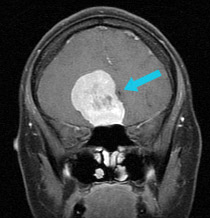

嗅沟脑膜瘤占颅内全部脑膜瘤的10%,在颅底前部眉毛和鼻子之间的颅腔深处形成。嗅沟脑膜瘤通常位于中线,但是随着尺寸的增大,它们可能会变得不对称。根据美国脑肿瘤协会(ABTA)的数据,嗅沟脑膜瘤通常是非癌性的,约占全部脑膜瘤的10%。根据国际卫生组织的脑膜瘤分类,它们几乎总是I级。如果您患有嗅沟性脑膜瘤,则在肿瘤长大之前,您可能不会出现任何症状。此位置的肿瘤可能会导致症状,例如嗅觉和味觉丧失,视力模糊,记忆力减退,头痛,疲劳,恶心和呕吐以及性格改变。由于症状并不总是存在,因此,我们通常会由于不相关的原因而执行磁共振成像(MRI)扫描后才发现嗅觉沟膜脑膜瘤。

尽管在影像学和治疗措施方面取得了进步,但在过去的几十年中,手术切除时这些肿瘤的平均大小并未改变。 嗅沟脑膜瘤约占全部基础脑膜瘤的14%。 发病高峰期在40至60岁之间,受影响的女性人数是男性的两倍。

手术治疗–嗅沟脑膜瘤的治疗主要是手术。这些肿瘤在出现症状之前已经达到了较大的尺寸,肿瘤的大小和鼻旁窦的侵犯是对其手术治疗的主要挑战。